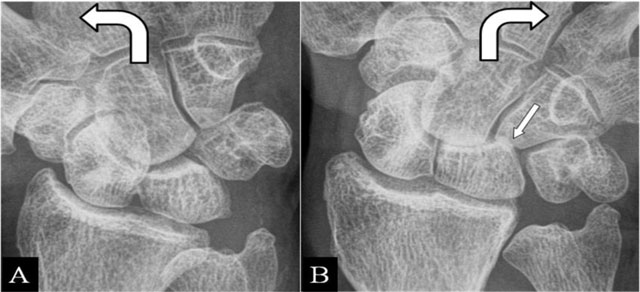

Fractures appear most frequently at the scaphoid waist [14]. Radial deviation gives an impaction at a pseudarthrosis. Contact zone deformation (Figure 6A and B) and mobility between the fragments are illustrated on radiographs. BMO and extrinsic ligamentous lesions are delineated by MRI.

Figure 6

(Intra)scaphoid abutment. (A, B) PA plain mobility radiographs in ulnar and radial deviation. (A) Large diastasis in ulnar deviation between the scaphoid bone fragments. (B) Impaction of both fragments in radial deviation. Associated midcarpal osteoarthritis (arrow).